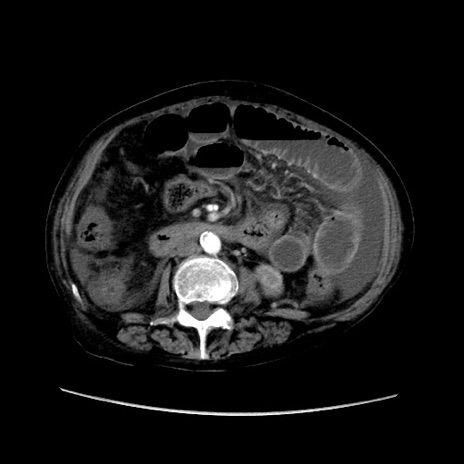

症例31(横断像)

【症例】80歳代 女性

【主訴】腹部膨満感

【現病歴】他院にて肝硬変にてフォロー中。1週間前から便秘、腹部膨満感、臍部腫瘤あり受診となる。

【既往歴】肝硬変

【身体所見】腹部膨隆あり、皮膚変化なし、疼痛なし。

【データ】WBC 4600、CRP 0.25